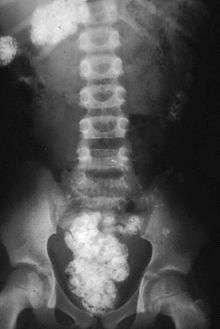

There are obvious health risks in the consumption of soil that is contaminated by animal or human feces; in particular, helminth eggs, such as Ascaris, which can stay viable in the soil for years, can lead to helminth infections.[28][29] Tetanus poses a further risk.[28] Lead poisoning is also associated with soil ingestion.[30]